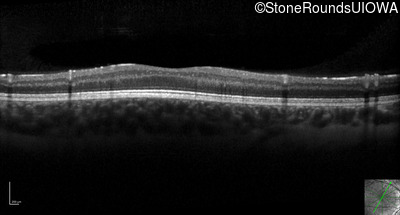

Optical Coherence Tomography - Right - 10/160 +1 sc

Exemplar / OCT Stack

Optical Coherence Tomography - Left - 10/200 sc